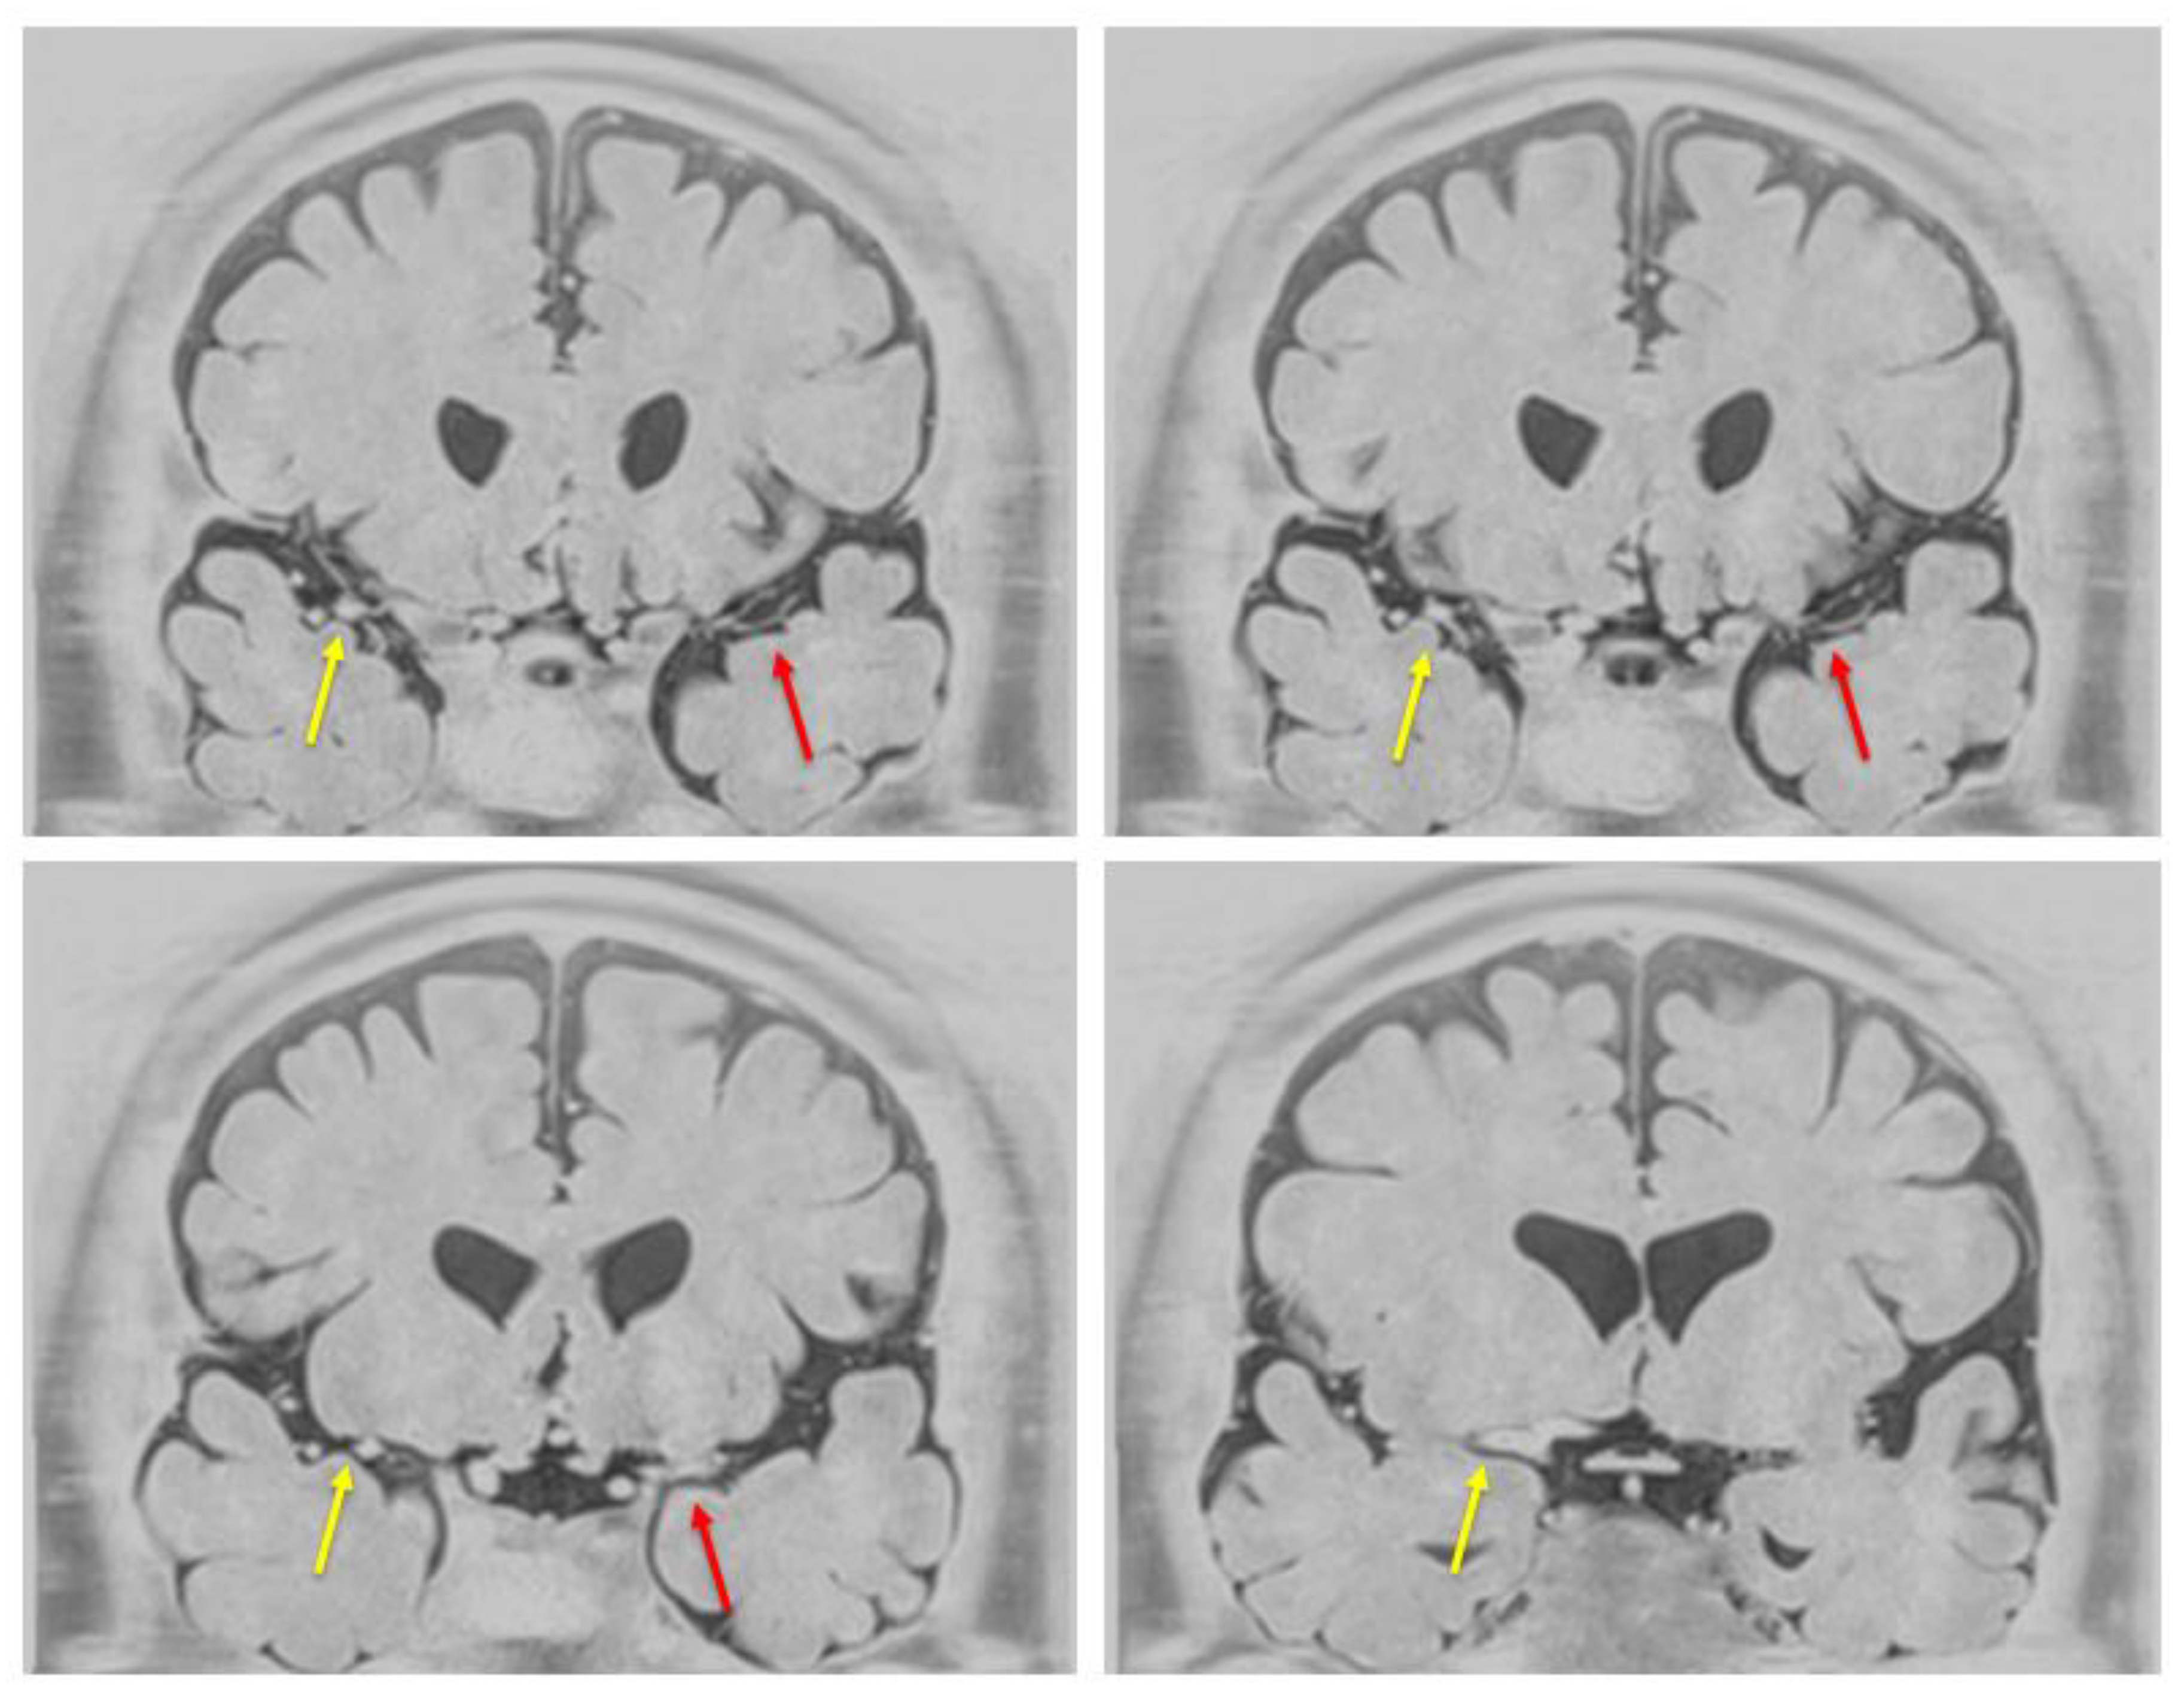

A 40-year-old male government employee sustained a head trauma while playing soccer. Approximately 2 months later, he experienced a gradually worsening headache and presented to our hospital. Head computed tomography (CT) revealed left-sided CSDH (Figure 1a), prompting admission. The patient had a medical history of right inguinal hernia repair, right-hand fracture, and papillary thyroid carcinoma at the ages of 10, 16, and 37 years, respectively, for which he underwent surgical resection only, with no radiation therapy, resulting in cure. Importantly, the patient had no prior history of radiotherapy, which is a known risk factor for moyamoya-like vasculopathy. Similarly, he had no history of hyperthyroidism. At 40 years of age, he was diagnosed with mild hypertension and treated with amlodipine monotherapy. Moreover, he had a smoking history of 10 cigarettes per day from the age of 17 to 38 years and occasionally consumed approximately one bottle of beer. There was no family history of Moyamoya disease or other cerebrovascular disorders. The patient underwent left burr hole irrigation and drainage on admission. His headache resolved promptly, and his CSDH was sufficiently drained (Figure 1b). He was discharged home 1 week later with a modified Rankin Scale (mRS) score of 0, and no CSDH was observed on postoperative month 1 (Figure 1c). After surgery for CSDH, the patient was relocated to work and continued to follow up at another hospital. A review of contrast-enhanced CT performed at the age of 37 years for the evaluation of a thyroid nodule 3 years before the head trauma demonstrated a symmetrical depiction of the MCA, with no evidence of vascular abnormalities (Figure 1d); additionally, imaging performed at 41 years of age (1 year after the CSDH) exhibited no evidence of MCA stenosis (Figure 1e). However, magnetic resonance angiography (MRA) revealed mild stenosis of the left MCA at the age of 43 years (3 years since CSDH) (Figure 1f), which gradually progressed over time. The stenosis had become severe at the age of 46 (6 years from CSDH) (Figure 1g). Moreover, at the age of 47 (7 years from CSDH) (Figure 1h, i), the left MCA was no longer visible on MRA, a finding that persisted at the age of 50 (10 years from CSDH). Susceptibility-weighted imaging (SWI) demonstrated multiple fine, punctate, and linear low-signal structures in the left basal ganglia (Figure 1j, k, l), consistent with Moyamoya-like collateral vessels characteristic of moyamoya-type vasculopathy.

Figure 1. Head computed tomography (CT) or magnetic resonance imaging showing chronic subdural hematoma (CSDH) or progression of left middle cerebral artery (MCA) stenosis. a: Preoperative head CT showing a left-sided chronic subdural hematoma with midline shift. b: Postoperative day 1 CT demonstrating resolution of the hematoma with adequate drainage and improved midline shift. c: CT obtained 1 month following surgery showing complete resolution of the hematoma and normalized brain contour. d: Reference contrast-enhanced CT at 37 years old before CSDH showing symmetrical bilateral middle cerebral arteries (MCAs) without stenosis. e: Contrast-enhanced CT at 41 years old, 1 year after CSDH, demonstrating no stenosis of the left MCA. f: MRA at 43 years old, 3 years after CSDH, demonstrating mild stenosis of the left MCA. g: MRA at 46 years old, 6 years after CSDH, showing significant progression of left MCA stenosis. h: MRA at 47 years old, 7 years after CSDH, revealing non-visualization of the left MCA. i: MRA at 50 years old, 10 years after CSDH, confirming continued non-visualization of the left MCA. j & k: SWI demonstrating Moyamoya-like collateral vessels in the left cerebral hemisphere suggestive of Moyamoya-like vascular networks. l: Magnified SWI view corresponding to panel (k), demonstrating abnormal fine collateral vessels in the left basal ganglia (arrows). These findings are characteristic of Moyamoya-type vasculopathy and were not observed on the contralateral side.